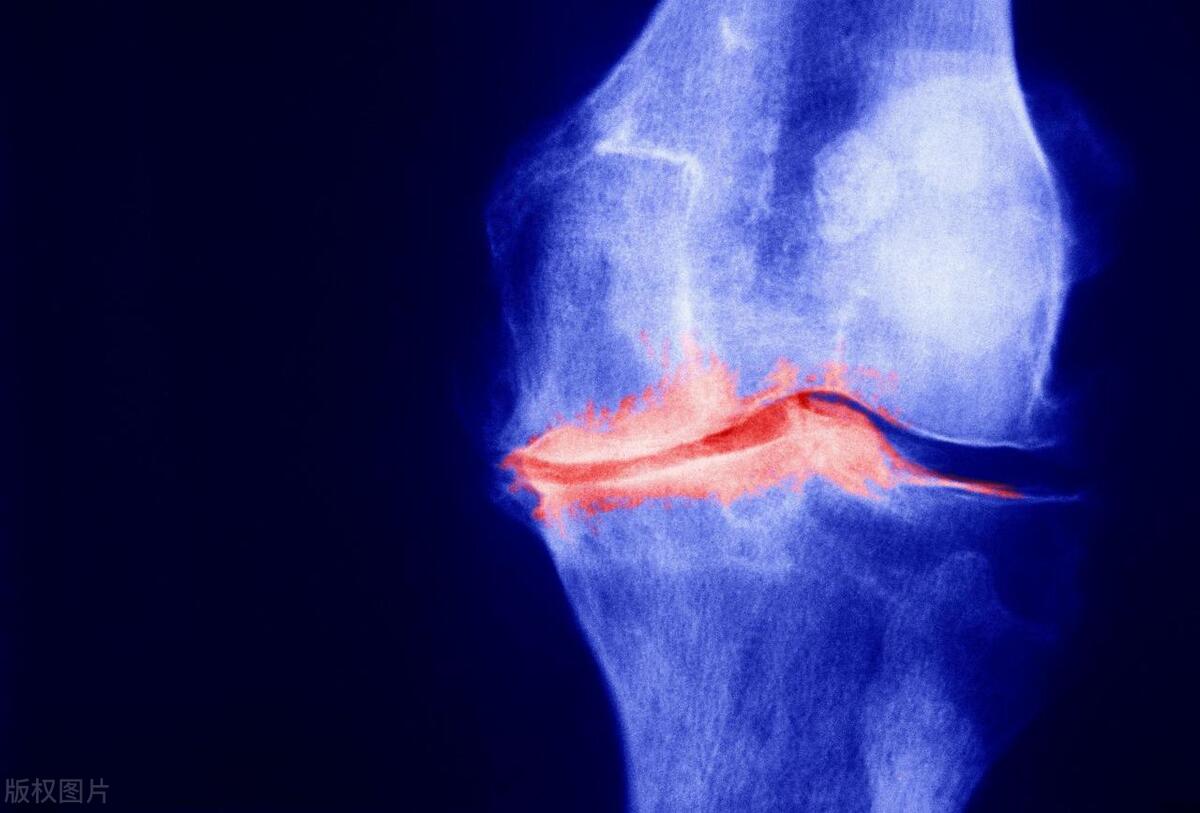

骨关节炎

关节软骨一旦缺损,就很难再生修复,只会越磨越少。得了骨关节炎的膝关节,关节软骨缺损,软骨下骨裸露,关节面不平整,容易发生无菌性炎症,引起膝关节疼痛。没有软骨的遮挡,就像窗户上没了玻璃,风寒便容易侵入骨质,膝盖便会怕风怕凉。